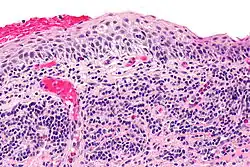

| Micrograph of plasmacytosis mucosae. H&E stain. | |

A biopsy is required to confirm the presumed clinical diagnosis. Histological alterations affecting the dermal vasculature and epidermis are typically identifiable. Pathological characteristics can include spongiosis, rete ridge loss, and epidermal atrophy. Single supra-basal layer epidermal cells have been characterized as lozenge or diamond-shaped keratinocytes. A dense inflammatory infiltrate of mostly plasma cells beneath the epidermis and an increase in vertically oriented capillaries are possible additional pathogenic signs. Additionally, erythrocyte extravasation and hemosiderin deposition are frequently seen. Notably, there is an absence of keratinocyte dysplasia and frank vesiculation.[9]